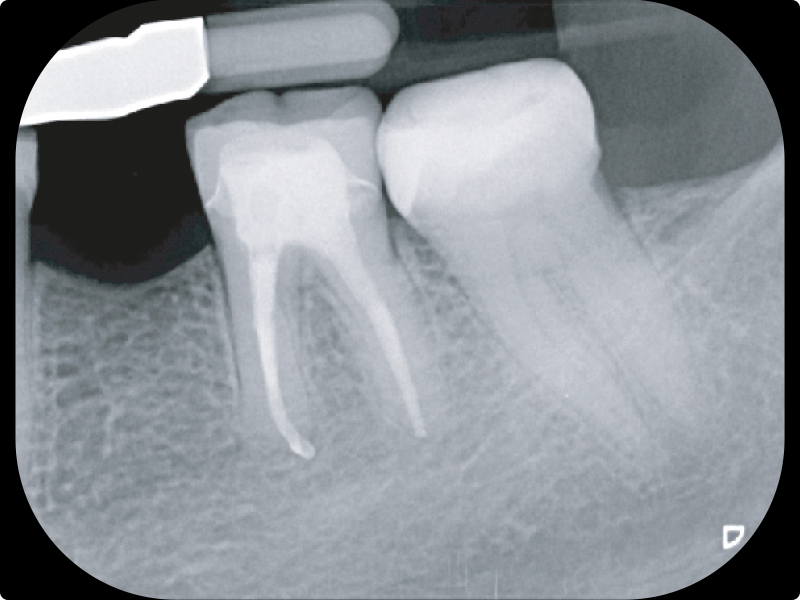

• La sagomatura moderna mini invasiva:

• rotazione continua e reciprocazione

• La sistematica ProcodileQ

• La sagomatura del canale radicolare con il sistema rotante FQ